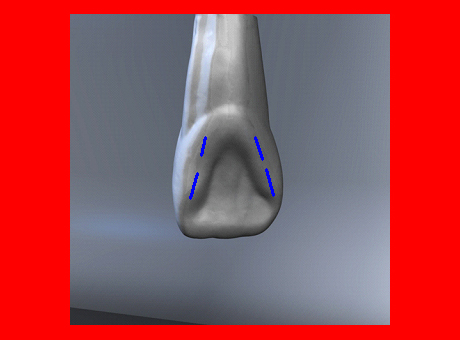

En ciertas áreas del saber humano, el lenguaje confuso o criptográfico Muchas son las técnicas elaboradas para lograr un desgaste selectivo, y numerosos autores han expuesto en su momento variadas formas de lograr una función oclusal fisiológica mediante el ajuste de la misma. Han pasado años desde entonces y, sin embargo, aún hoy, un altísimo porcentaje de profesionales “navega” por el mar de la confusión oclusal, dada la diversidad de conceptos y escuelas, sin lograr arribar a costa alguna donde poder anclar un conocimiento sólido sobre cómo tratar la oclusión Ya se esté realizando una simple obturación, endodoncia, incrustación, radectomía u ortodoncia, la lógica pocas veces, en la mayoría de los casos, vincula un tratamiento con otro, siendo el resultado final el mismo caos inicial; enmascarado por mucho tratamiento profesional. El ajuste oclusal es un medio inicial de proveer al sistema enfermo de: Dicha técnica, que puede ser terapéutica en sí misma; consta de dos etapas, a saber: 1) Ajuste Oclusal por Adición Mediante el estudio de la guía anterior, encargada de efectuar las Disclusiones durante las excursiones mandibulares, podremos observar si ésta es funcional o no. • Marcas de carácter continuo, si en ese recorrido se produce la Disclusión de los sectores posteriores y todo marcha correctamente. FIG 1-2 Si por el contrario observamos: • Marcas de carácter discontinuo, significa que dicha Disclusión se está efectuando por medio de una pieza dentaria posterior a la guía anterior. FIG 3-4-5 (FIGS. 3, 4 Y 5). En la figura 6 las flechas indican, en un caso clínico de análisis oclusal, la presencia de marcas discontinuas que indican Interferencias en Propulsiva. FIG 6-7 Y por último, si existieran: • Abrasiones de las áreas discluyentes en las áreas de diagnóstico de la guía anterior, deberemos aportar material a dicha zona para no permitir el choque lateral de las piezas posteriores (Ajuste Oclusal por Adición) En las imágenes 11 y 12 podemos observar la adición de composite en la punta de un canino derecho, previa la observación de la Faceta Parafuncional remarcada durante el análisis oclusal en el articulador. (FIGS. 8 A 12). 2) Ajuste oclusal por Sustracción o Desgaste Habiendo cumplido ya con la verificación de la funcionalidad de la Guía Anterior, comenzamos los desgastes en céntrica, a fin de lograr un único arco de cierre, guiado eficazmente por la Guía Anterior; es decir: la coincidencia entre Oclusión Habitual y Oclusión en Relación Céntrica. En este caso, intentar gastar dichos puntos, de ser posible sólo en las cúspides de corte o no fundamentales: • Crestas Triangulares Internas, Cúspides Vestíbulares Superiores • y un poco de las Crestas Triangulares Internas, Cúspides (FIGS. 13 A 16). Si la deflección es hacia el lado opuesto, se invierten los desgastes. En las migraciones hacia adelante, las únicas razones posibles están en los puntos estabilizadores (FIG. 17); es decir: -Vertientes Distales de los Rebordes Marginales, Triangulares (FIG 17) (FIG 18 A-B-C-D) Obsérvese cómo, en una boca prácticamente entera, comienzan a “desmoronarse” prismas adamantinos (FIG. 19), como consecuencia de un punto prematuro de contacto, ubicado en la posición de un estabilizador, que provoca la discrepancia horizontal postero-anterior causante de dicho efecto (FIG. 20). FIG 19-20 Dicho punto, será necesario ajustarlo antes de cualquier tratamiento en la zona ¿Cuáles serían las consecuencias si esos incisivos fueran implantados tal como es frecuente observar en múltiples congresos y cursos de implantología, donde el tema de la oclusión no es más que un cuadro polifacético y anecdótico? 14 15 16 17 Todo producto del adelantamiento mandibular Realizados ya los desgastes en céntrica, obteniendo de esta manera un único arco de cierre, es decir, oclusión en relación céntrica, debemos realizar el ajuste de las excéntricas, apoyando la acción de la guía anterior, para lo FIG 22 a. De un lado a otro de un mismo maxilar, la imagen es especular, o sea invertida. b. En hemimaxilares cruzados, la imagen es idéntica. Allí donde existan colisiones entre cúspides, se deberá crear un surco para que dicha cúspide antagonista migre a su través, tanto en el lado de no trabajo, como en el de trabajo y en el de propulsión. FIG 23 Es importante conservar esta parte del surco, ya que si no existieran, los contactos entre cúspides serían en superficie y no puntiformes (fig. 24). FIG 24 1. Obtener un único arco de cierre con coincidencia entre oclusión habitual y relación céntrica. 2. El cierre mandibular debe ser recibido sólo por la tabla premolar-molar. 3. Durante las excursiones funcionales es la guía anterior la que debe sufrir las fuerzas laterales. 4. De cumplirse estas dos premisas debemos obtener libertad de desplazamiento (no confundir con libertad en céntrica) a las piezas posteriores mediante la creación de surcos disclusivos. Examinadas ya las posibles migraciones mandibulares y los desgastes o aposiciones necesarios para poder ocluir en céntrica, es fundamental recordar que, previamente a todo tipo de ajuste, se ha hecho necesario ubicar a la mandíbula en relación céntrica. Para ello debemos utilizar el propio funcionalismo muscular 22 FIG 25 Y esto no significa otra cosa que: piezas dentarias estables en todos los planos del espacio, ATM centrada en la cavidad glenoidea, periodontos sin tensión, músculos en la dimensión de elongación adecuada para un fisiologismo Paz absoluta en la intimidad del Sistema Estomatognático. Y así, como corolario final, es posible establecer una regla de oro similar en importancia a la conocida formula: Forma = Función Ésta es: FIG 26 FUNDAMENTOS NEUROFISIOLÓGICOS DEL REGISTRO DE OCLUSIÓN EN RELACIÓN CÉNTRICA ( ORC) MEDIANTE EL USO DE LAMINILLAS DE LONG CUADRO

En el transcurso de dichas Lateralidades o Propulsiva, podremos ver:

En la figura 7, se muestran la Disclusión Inicial (durante el transcurso de la cual deben separarse por completo los sectores posteriores –flecha izquierda–, y la Disclusión Final de recorrido mucho más largo –flecha derecha–.